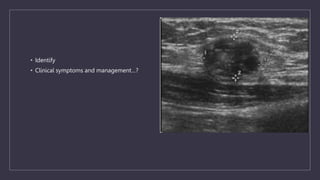

• Identify

• Clinical symptoms and management…?